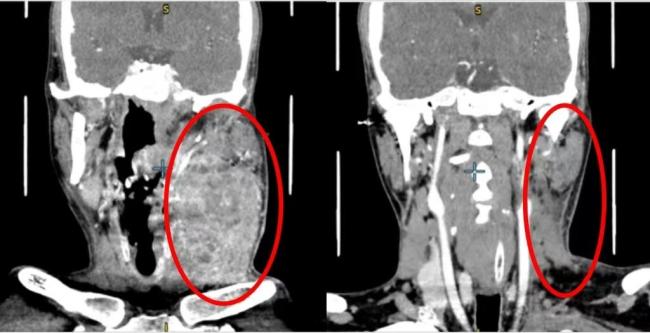

上海第九东谈主民病院口腔颌面-头颈肿瘤科接诊了这名33岁的患者。从发现舌头左侧有溃疡到来病院看病,前后仅2个多月时分。此时,患者的口腔溃疡不仅莫得愈合,反而赶快发展,彭胀到了悉数这个词舌头再到下颌,不仅舌头动不了,嘴巴也张不开,吃东西费事。肿瘤还从舌头搬动到了颈部,径直包住了左侧颈动脉,属于晚期高危病东谈主。

经由两个月的药物治愈,星空体育患者肿瘤彰着减弱后,手术施伸开展。在麻醉科、病理科、养分科、影像科等多学科大家的匡助下,手术历经10多个小时,患者顺利继承了左舌颌双颈纠合根治术,同时还完成了自体组织移植,进行舌和颈部设置手术。手术中切掉了4/5的舌头,并取患者大腿外侧皮肤肌肉血管组织进行修补,以减少术后并发症的风险。